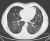

De oorzaken van PAP zijn lang niet altijd duidelijk. Als de aandoening bij kinderen optreedt, is er meestal sprake van erfelijkheid. Bij volwassenen wordt PAP bijna altijd veroorzaakt door een auto-immuunziekte. Hieronder ziet u hoe longen waarin eiwit zich heeft opgehoopt (PAP) er op de CT-scan uitzien.